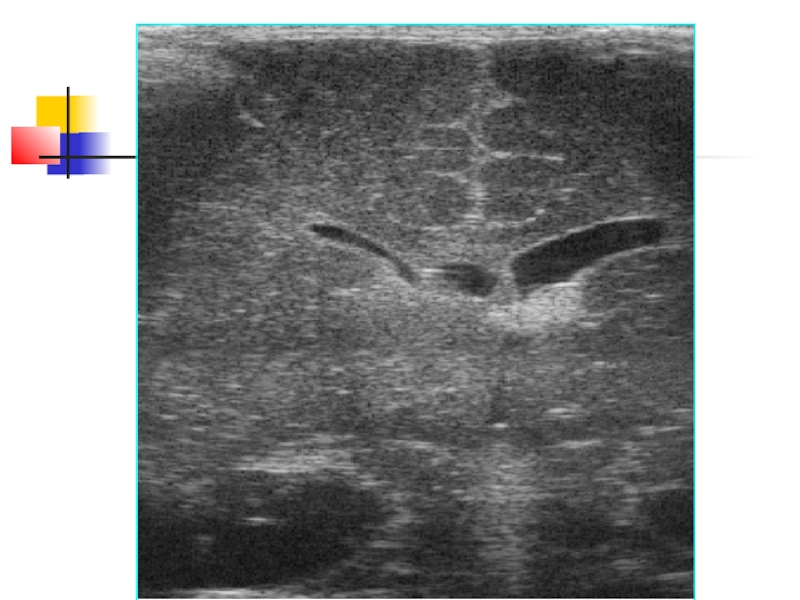

Слайд 35передний рог левого бокового желудочка

полость

прозрачной перегородки

III желудочек

передний рог правого

бокового желудочка

фрагменты ликворных путей,

визуализируемые в стандартном

фронтальном скане,

имеют

собственное название:

«тюльпан»

передний рог левого бокового желудочкаполость прозрачной перегородкиIII желудочекпередний рог правого бокового желудочкафрагменты ликворных путей, визуализируемые в стандартном